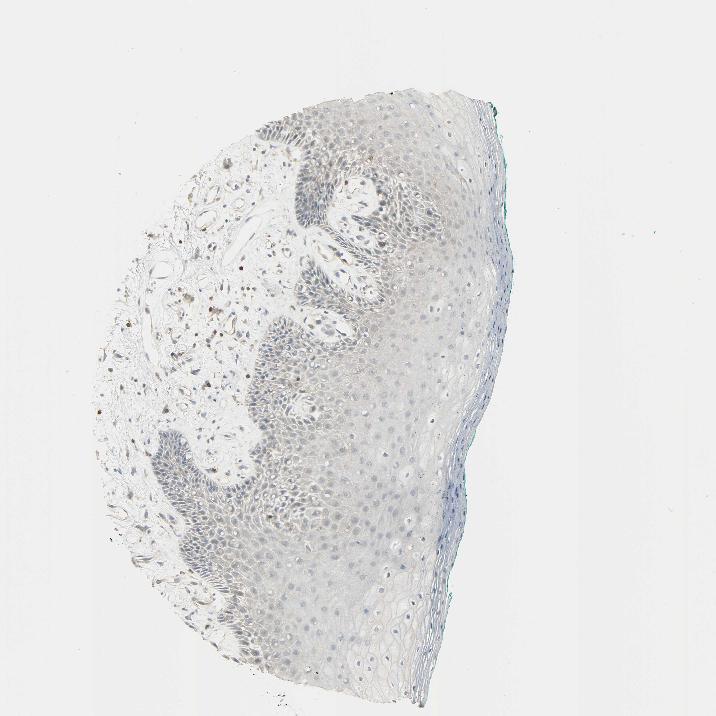

TISSUE PRIMARY DATA ORAL MUCOSA Show tissue menu

ORAL MUCOSA - Antibody stainingi

Antibody staining in the annotated cell types in the current human tissue is reported as not detected, low, medium, or high, based on conventional immunohistochemistry profiling in selected tissues. This score is based on the combination of the staining intensity and fraction of stained cells.

Each image is clickable and will lead to virtual microscopy that enables deeper exploration of all samples and also displays staining intensity scores, fraction scores and subcellular localization as well as patient and tissue information for each sample.

Antibody HPA004252Antibody HPA004472Antibody CAB000011Antibody CAB068180

Squamous epithelial cells LowNot detectedNot detectedNot detected